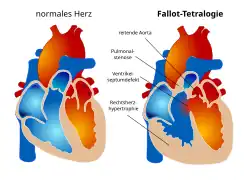

Die Fallot-Tetralogie (auch Fallot’sche Tetralogie) ist eine angeborene Herzfehlbildung, die etwa 6–7 % der angeborenen Herzfehler ausmacht. Sie besteht aus vier Komponenten (daher Tetralogie): einer Pulmonalstenose, einem Ventrikelseptumdefekt (Defekt in der Herzscheidewand), einer über der Herzscheidewand reitenden Aorta sowie einer nachfolgenden Rechtsherzhypertrophie. Die auch im Deutschen bei Medizinern gebräuchliche Abkürzung TOF leitet sich aus dem Englischen Tetralogy of Fallot ab. In etwa einem Drittel der Fälle treten neben den Herzveränderungen weitere Fehlbildungen auf, vor allem am Verdauungstrakt sowie Spalten.[1]

Eigentlich liegen bei dieser Fehlbildung keine vier separaten Defekte vor, sondern ein einziger, nämlich eine Verlagerung der infundibulären Scheidewand der rechten Herzkammer nach vorn.[6]

Am Ende der fünften Entwicklungswoche entspringt die Ausstrombahn des Herzens noch aus beiden Herzhälften. Durch Ausbildung von Endokardwülsten im Conus cordis entsteht das Septum aorticopulmonale, das den Conus cordis in rechte und linke Ausstrombahn teilt (Aorta und Truncus pulmonalis). Verlagert sich jedoch das Septum aorticopulmonale nach vorne, verengt sich das Kammerausflussgebiet (Pulmonalstenose), das Septum ist allerdings noch geöffnet (Ventrikelseptumdefekt). Die Aorta entspringt nun aus beiden Herzkammern (reitende Aorta). Durch die Pulmonalstenose kommt es zu Bluthochdruck (arterielle Hypertonie) in der rechten Herzkammer. Damit noch genügend Blut aus dem Herzen gepumpt werden kann, vergrößert sich die Kammerwand (hypertrophierter rechter Ventrikel).

Die Fehlbildungen

Folgende Fehlbildungen bilden das Krankheitsbild:

Pulmonalstenose

Die Pulmonalstenose als Verengung des Ausgangstraktes der rechten Herzkammer zur Lunge. Die einzelnen Anteile dieses Ausflusstraktes (herznaher Anteil, Klappenring mit halbmondförmigen Klappen (semilunares) und lungennaher Anteil) können unterschiedlich stark verengt sein. Die eigentliche Pulmonalklappe ist häufig missgebildet und weist in über 60 % der Fälle nur zwei Halbmondklappen auf. Deshalb kann der Schweregrad der Klappenverengung sehr stark variieren. Das Pulmonalgefäßsystem ist - entsprechend den Verengungen im gesamten Ausflusstrakt - in der Regel unterentwickelt.

Ventrikelseptumdefekt

Der Ventrikelseptumdefekt ist ein Loch in der Scheidewand zwischen den Herzkammern, der bei der Fallot-Tetralogie nicht ein Mangel an Substanz der Kammerscheidewand ist, sondern durch die Fehlbildung des Herzens entstand. Er liegt meist direkt unterhalb des rechtsventrikulären Ausflusstraktes (Pulmonalklappe) und in der Nähe der Aortenklappe (Auslassklappe für den Körperkreislauf) und der Trikuspidalklappe (Klappe zwischen rechter Hauptkammer und rechter Vorkammer).

Überreiten der Aorta

Durch eine mangelhafte Rotation des Pulmonalgefäßes in der Herzentwicklung bleibt die Aortenwurzel in ihrer Beziehung zur rechten Herzkammer positioniert, so dass ein „Überreiten der Aorta“ über dem Ventrikelseptumdefekt resultiert.

Rechtsherzhypertrophie

Die Rechtsherzhypertrophie, ein die Herztätigkeit behindernder Zuwachs der Muskelmasse des rechten Herzens aufgrund der chronischen Überbelastung, kann anfangs gering sein, jedoch im Laufe der Zeit zunehmen.